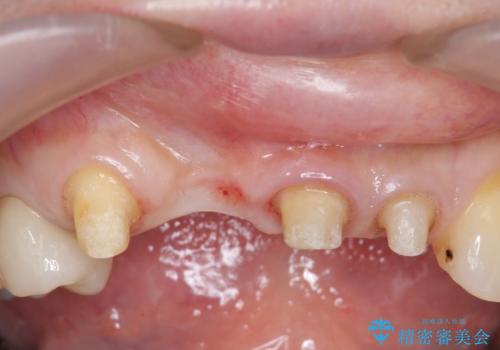

- 下顎前歯部の突き上げで上顎前歯の被せ物が土台ごと外れてしまった方の症例です。

右上1番目の歯は根元まで割れてしまっており、保存不可能だったため抜歯となりました。

抜歯後、骨と歯肉の回復を待ち、オールセラミッククラウンによるブリッジで補綴を行いました。